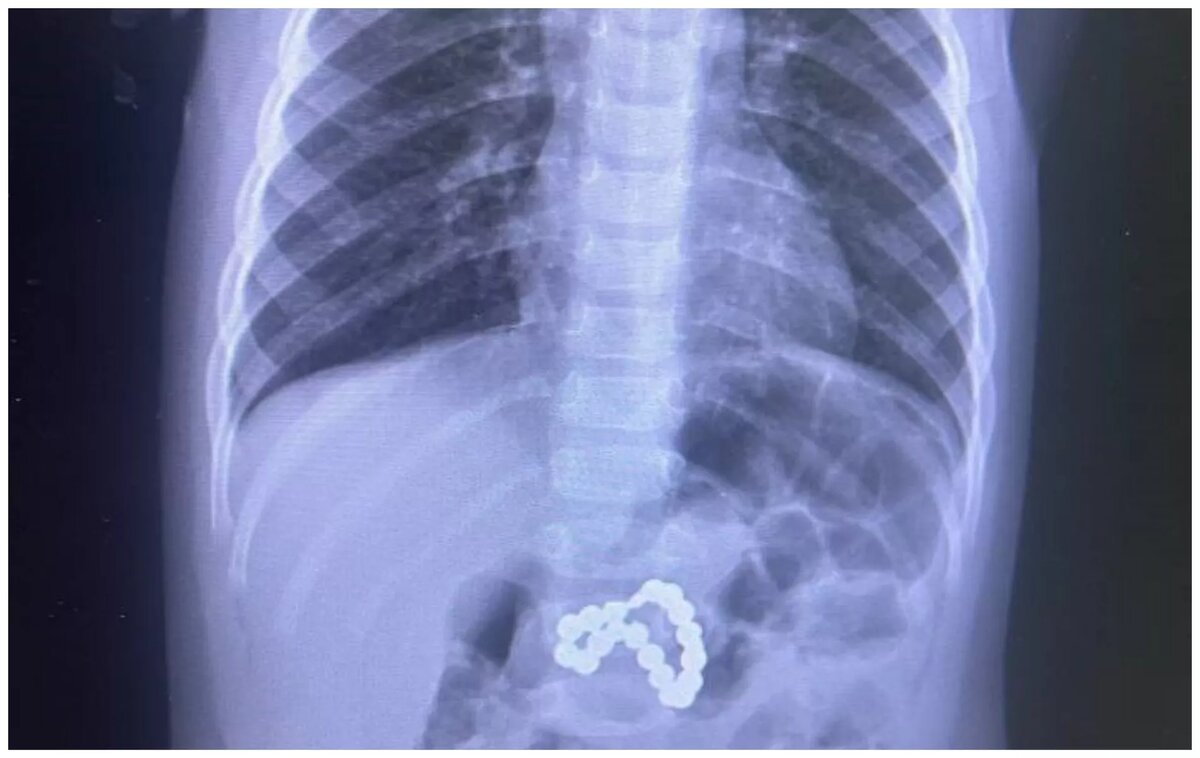

Врачи из Югры спасли жизнь девочке, которая проглотила магниты

В Югре удалось спасти девочку, которая проглотила магниты. Операцию провели врачи Центра охраны материнства и детства Сургута. Подробностями поделилась президент центра Лариса Белоцерковцева в личном telegram-канале.

Действовать пришлось быстро. Ребенка госпитализировали в тяжелом состояние. Девочке сразу же сделали эндоскопию. Выяснилось, что магниты повредили ей и желудок, и кишечник.

Было решено проводить экстренную операцию. Врачи ушили перфорацию. Также были проведены реанимационные мероприятия и переливание крови. Ребенка удалось спасти.